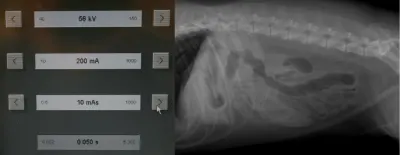

Remember to develop the films with fresh, clean developing solutions-old or exhausted developer will not work for developing technique charts. Examine the films for the setting that gives the best diagnostic quality. In Figure A, the kVp was 56, mA setting was 200, and time was 0.0125 seconds (mAs = 2.5). In this example, the bones are not easily visualized and the film overall is too white (underexposed).

In Figure B, the kVp and mA were left the same and the time was changed to 0.025 seconds (mAs = 5). In this image, the body wall, abdominal organs, and bones can all be readily visualized; this is a proper exposure. In Figure C, the kVp and mA were left the same and the time was changed to 0.05 seconds (mAs = 10). With this higher exposure technique, the ventral body wall cannot be visualized, and the abdomen is too dark (overexposed).